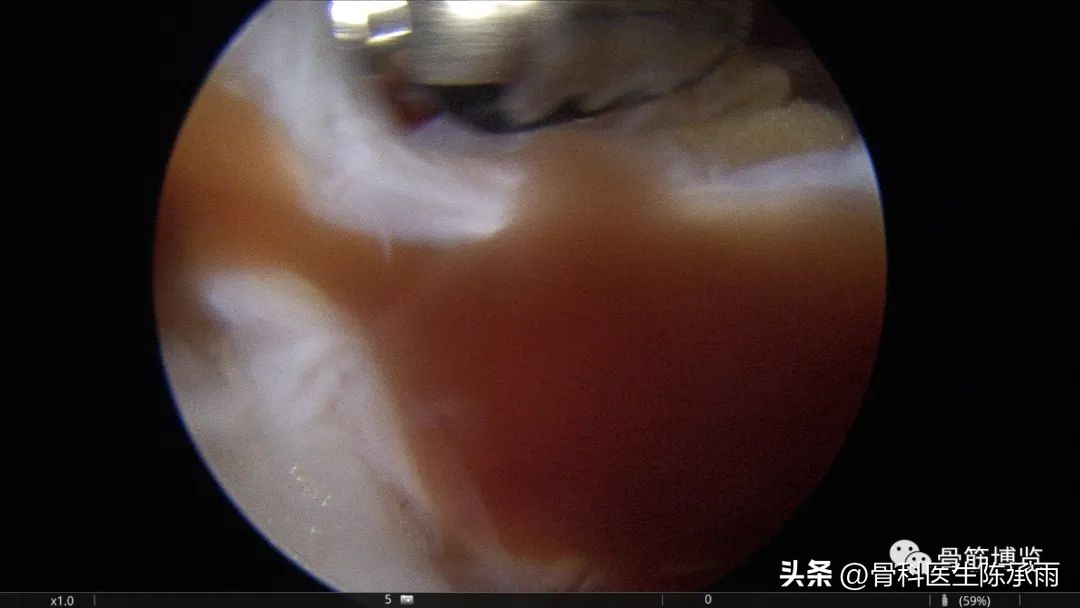

本例为内侧半月板前角巨大囊肿,关节镜下行半月板囊肿引流减压+囊肿前壁及囊壁滑膜切除+半月板缝合术。术中切除全部囊壁内滑膜及前壁及大部分后壁,保留部分后壁组织,以保证半月板前角缝合可靠及稳定。

术中情况

半月板囊肿分型决定了治疗方法的选择,对于前两种半月板囊肿因伴有半月板的损伤治疗方法相对复杂,半月板囊肿合并的半月板损伤多为水平撕裂或复杂撕裂,而且病史较长,因此需严格掌握缝合手术的指证。手术操作要点:采用常规的髌下内侧和髌下外侧入路,探查关节内囊肿和半月板撕裂的大致范围;使用刨刀细致地将囊肿切除,尽量彻底切除囊壁,充分敞开囊腔,避免囊肿复发,囊肿内可有分房或分隔现象,注意避免遗漏。注意在手术时尽量保留冠状韧带,避免冠状韧带的广泛缺损;进一步仔细探查损伤的半月板组织,明确撕裂的范围在红﹣红区或红﹣白区,对于超出上述范围的损伤或半月板的复杂撕裂及水平撕裂,放弃缝合手术,如条件许可时可在切除部分半月板(如切除水平撕裂的两片中不稳定的一片)的基础上进行缝合手术。然后以刨刀或磨钻小心修整损伤的半月板组织,使对合面整齐并显露新鲜组织;髌下外侧人路置人工作套管,附加经髌韧带的正中入路,严格解剖复位。经正中人路置人探针,固定半月板撕裂部位,使用肩袖缝合器经髌下外侧入路工作套管,缝合器尖端首先由半月板前缘和冠状韧带的交界处穿人半月板下表面后,越过半月板裂隙,在对侧由下到上穿出半月板上表面,经工作套管将线导出,体外打 Duncan 结,推线器将线结推人至半月板前缘处拉紧,再打两个套结,剪断缝线。两缝线之间间距8 mm 。滑膜囊肿的手术操作相对简单:镜下切除囊肿后,将半月板与冠状韧带之间的缺损区缝合。